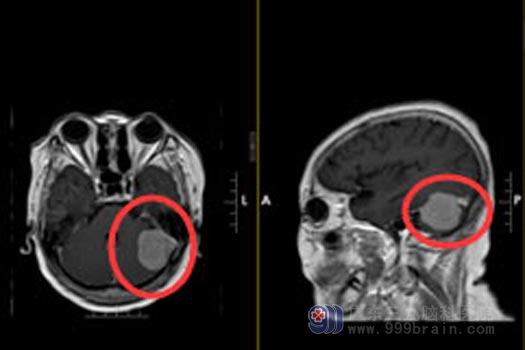

广东三九脑科医院综合神经外科进一步检查提示:左侧枕部跨小脑幕上下占位病变,考虑脑膜瘤,范围约3.3cm×3.3cm×4.0cm。

手术前